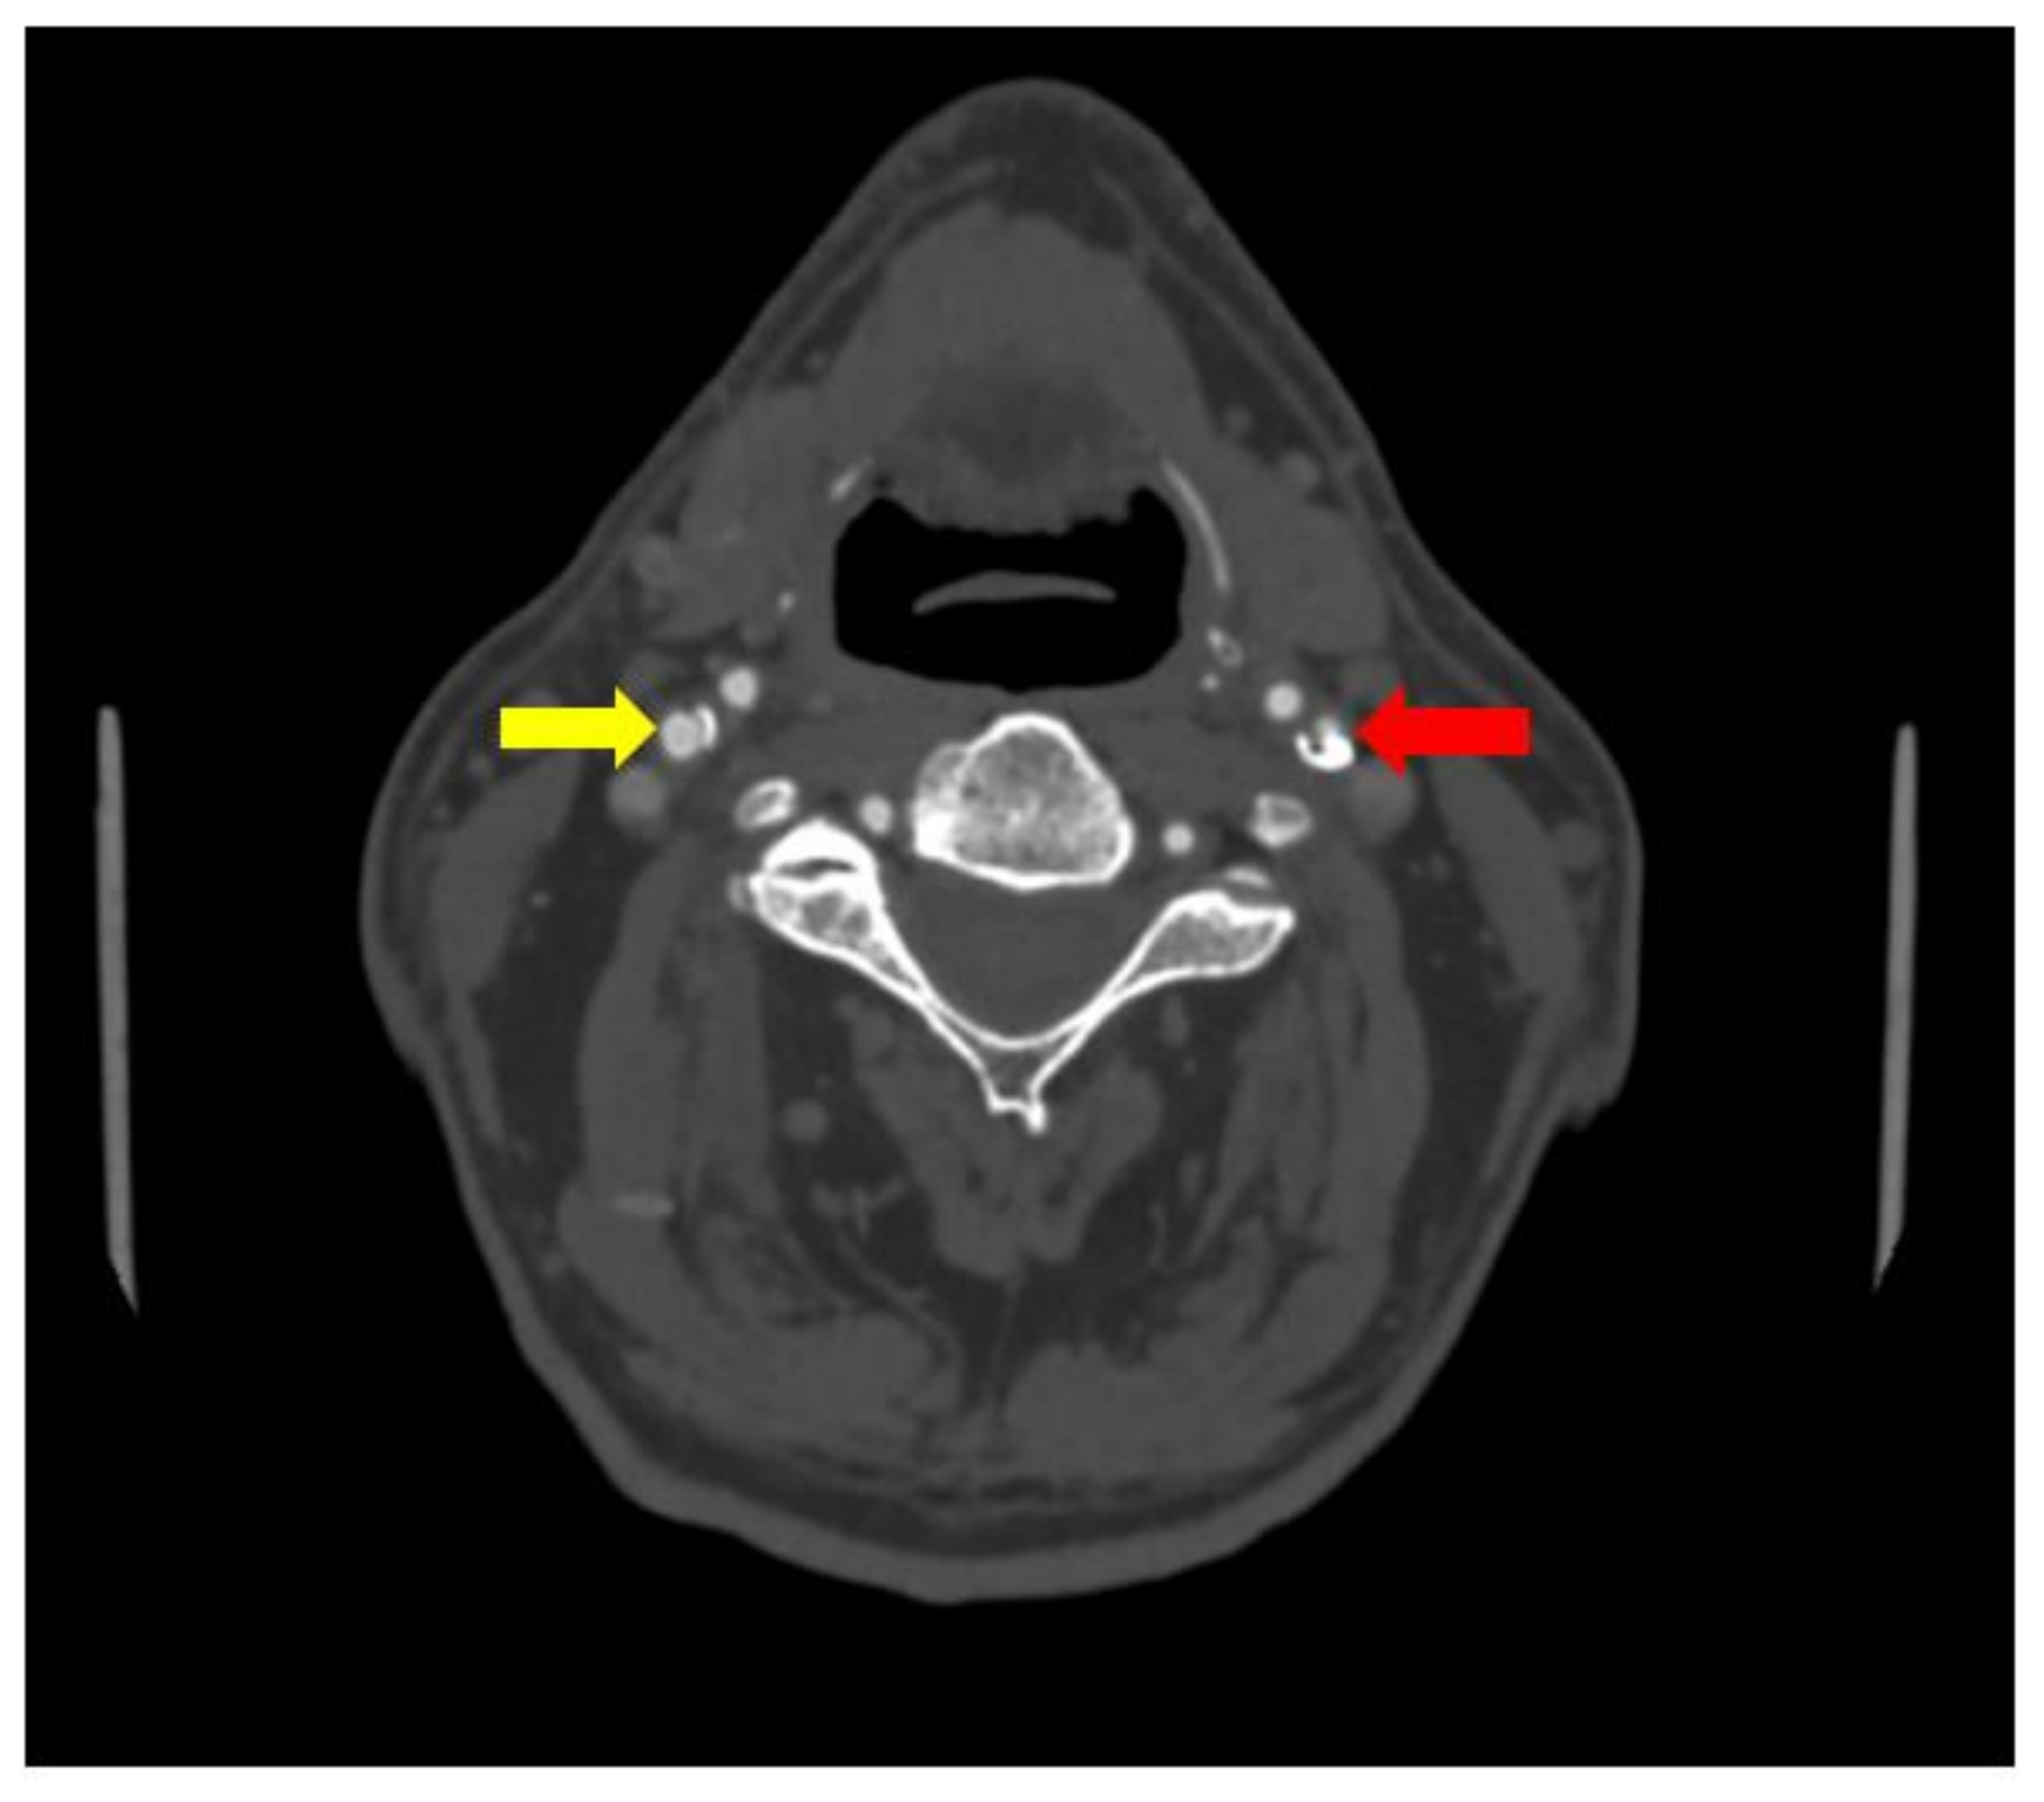

No significant changes were noted in the patient blood tests and patient urine analysis. When performed computed tomography angiography (CTA), subocclusion in the proximal segment of the left internal carotid artery was seen, as well as 30% stenosis in the proximal segment of the right internal carotid artery was observed (see Figure 1 and Figure 2).

Figure 1. Subocclusion in the proximal segment of the left internal carotid artery (CTA) (red array).